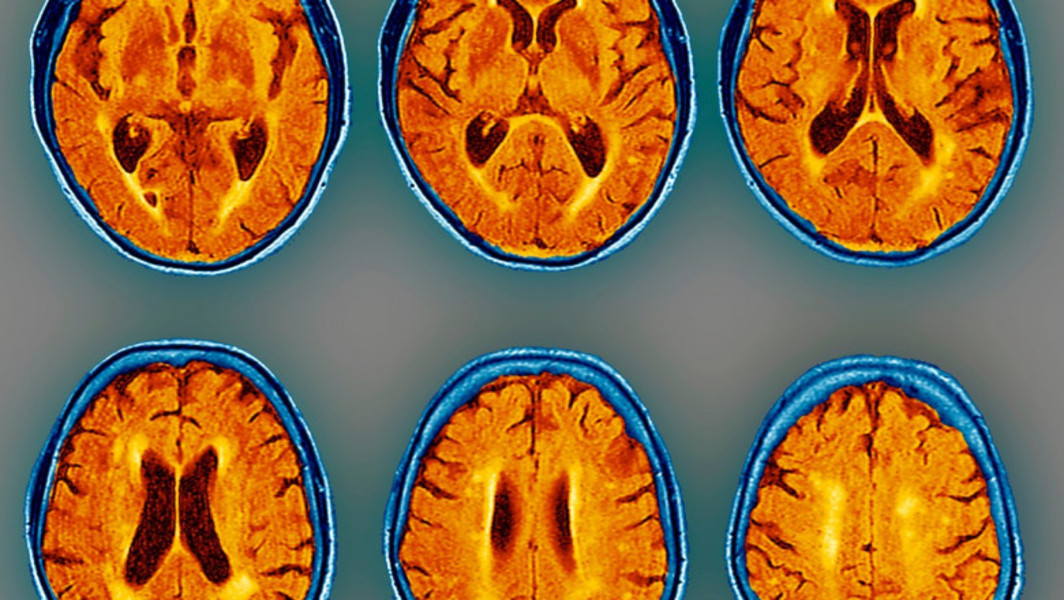

Peste 153 de milioane de oameni vor suferi de demență până în anul 2050, potrivit unui nou studiu. Autorii studiului publicat în The Lancet spun că datele sunt socante, iar demenţa reprezintă „o ameninţare majoră, care se dezvoltă rapid”, punând presiune pe sistemele de sănătate şi asistenţă socială în fiecare ţară în parte.